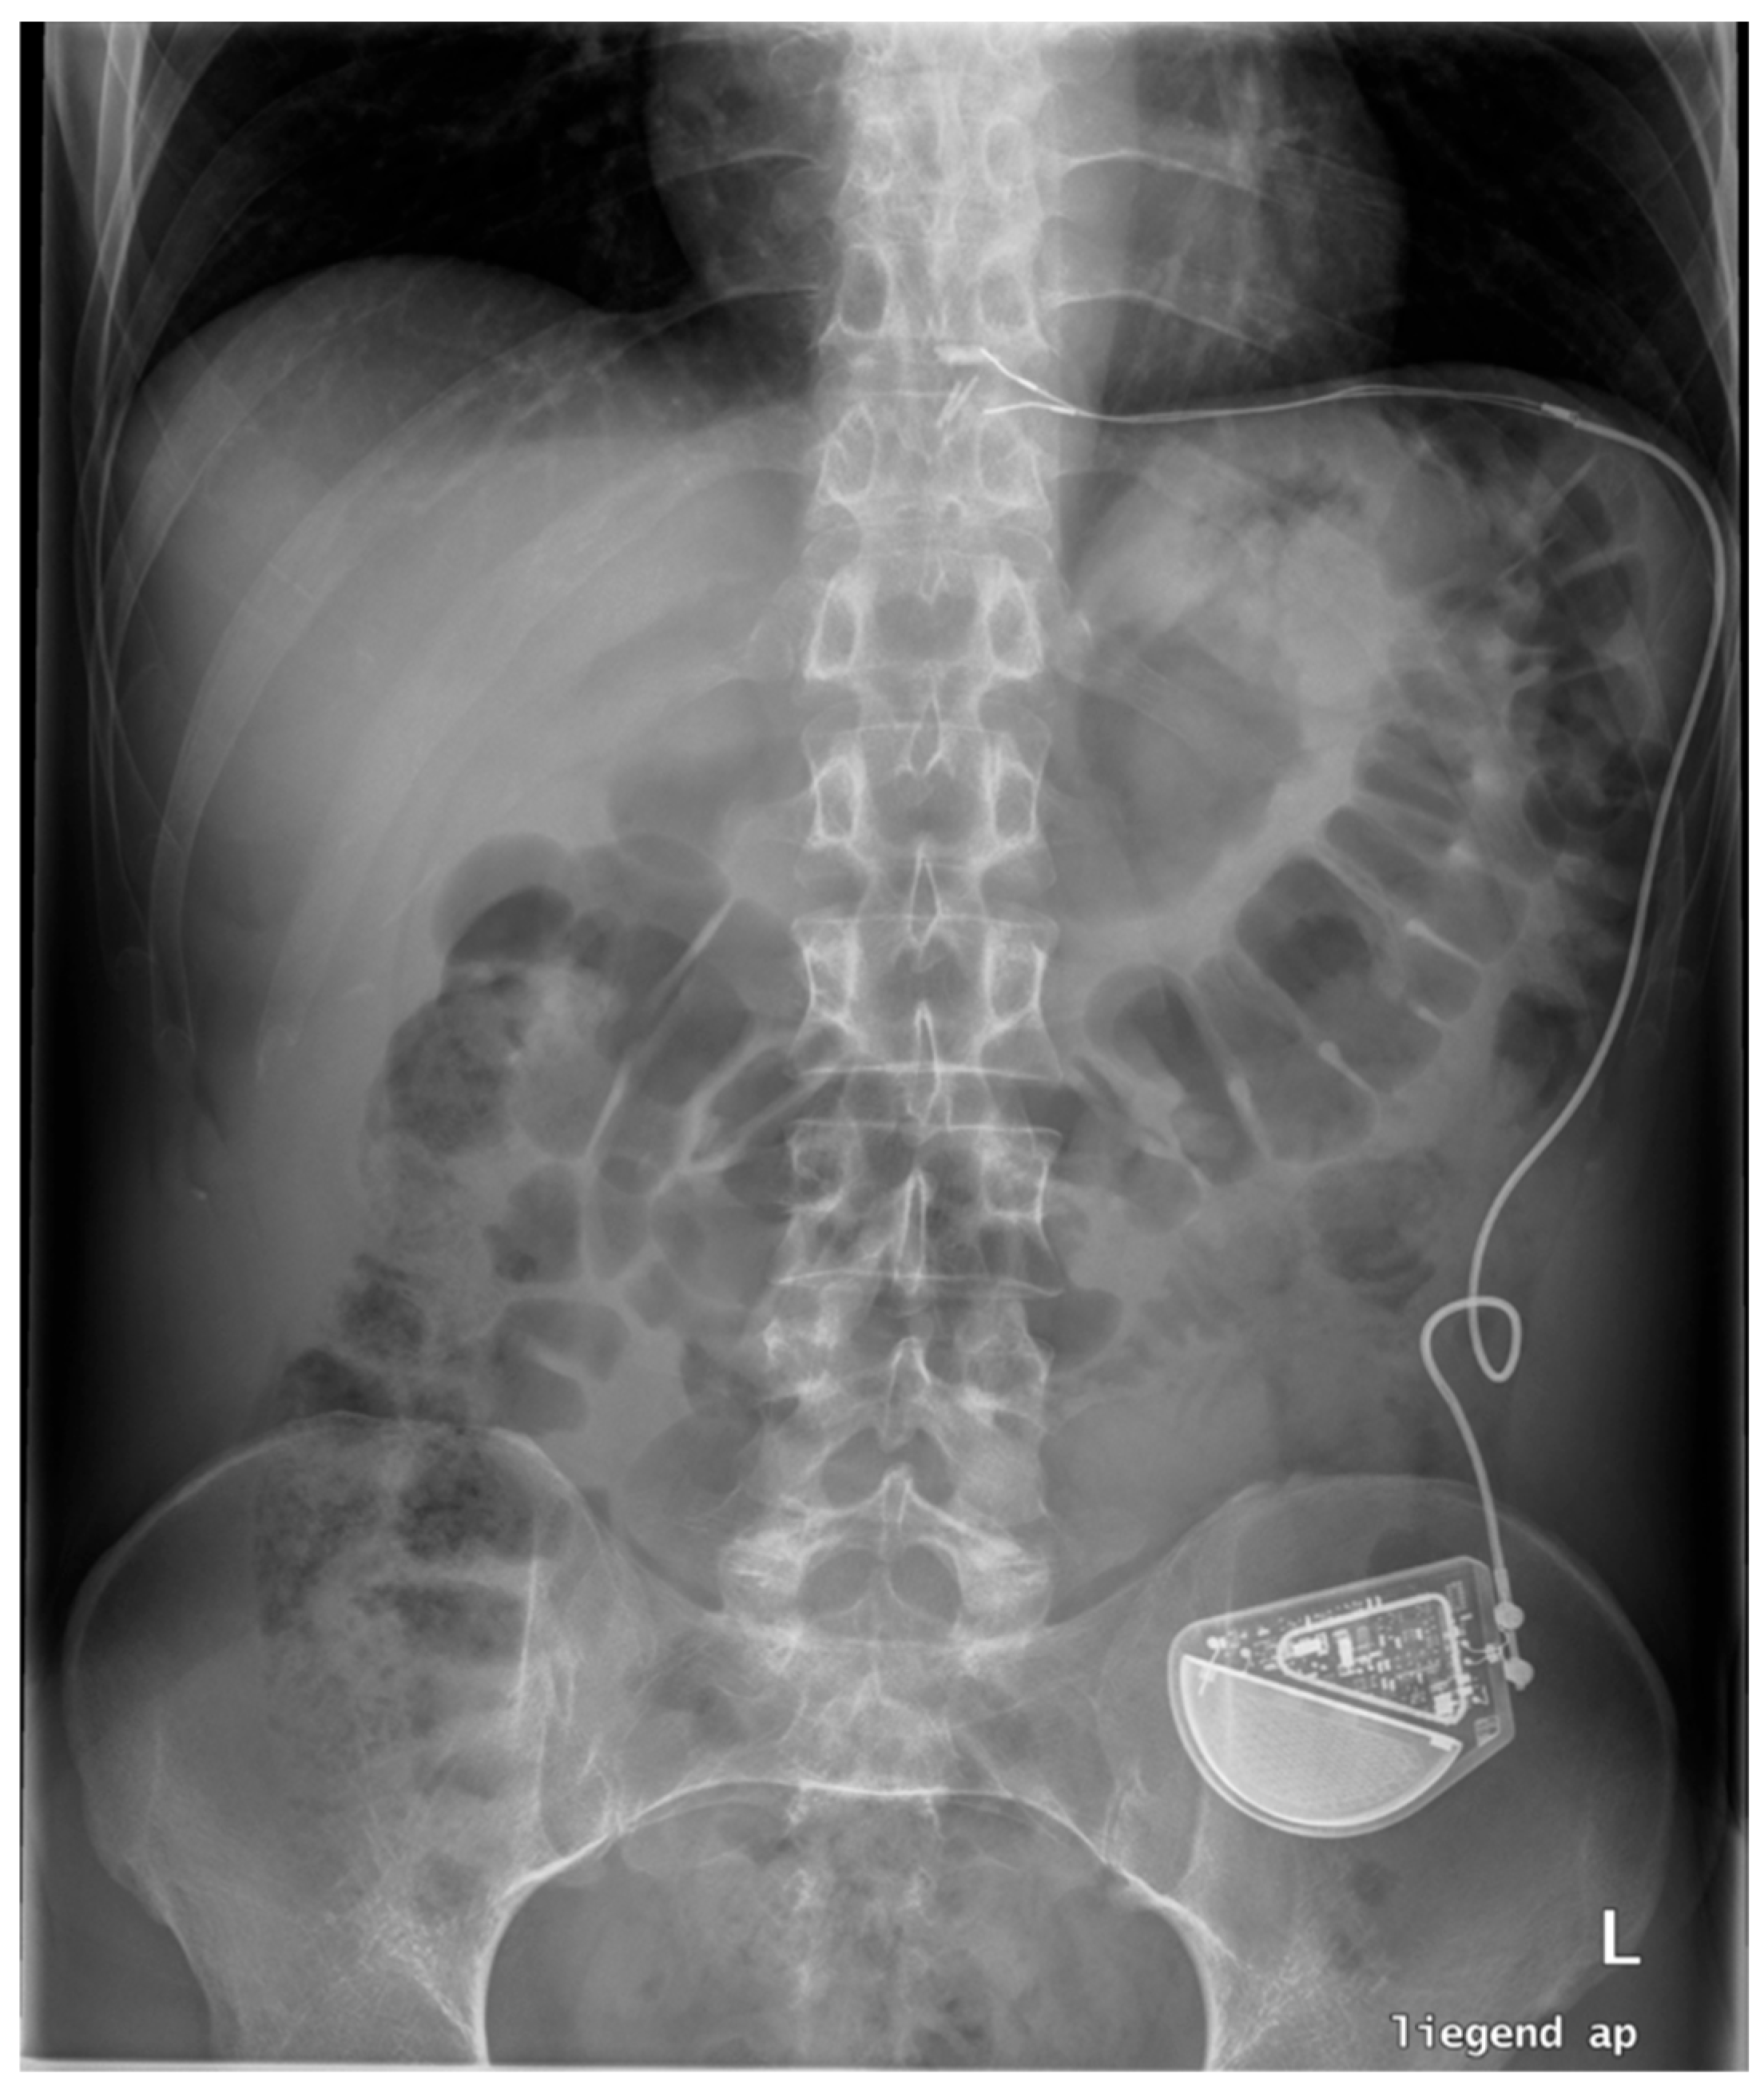

18. Electrical Stimulation (EST)

19. RefluxStop™

20. Conclusions